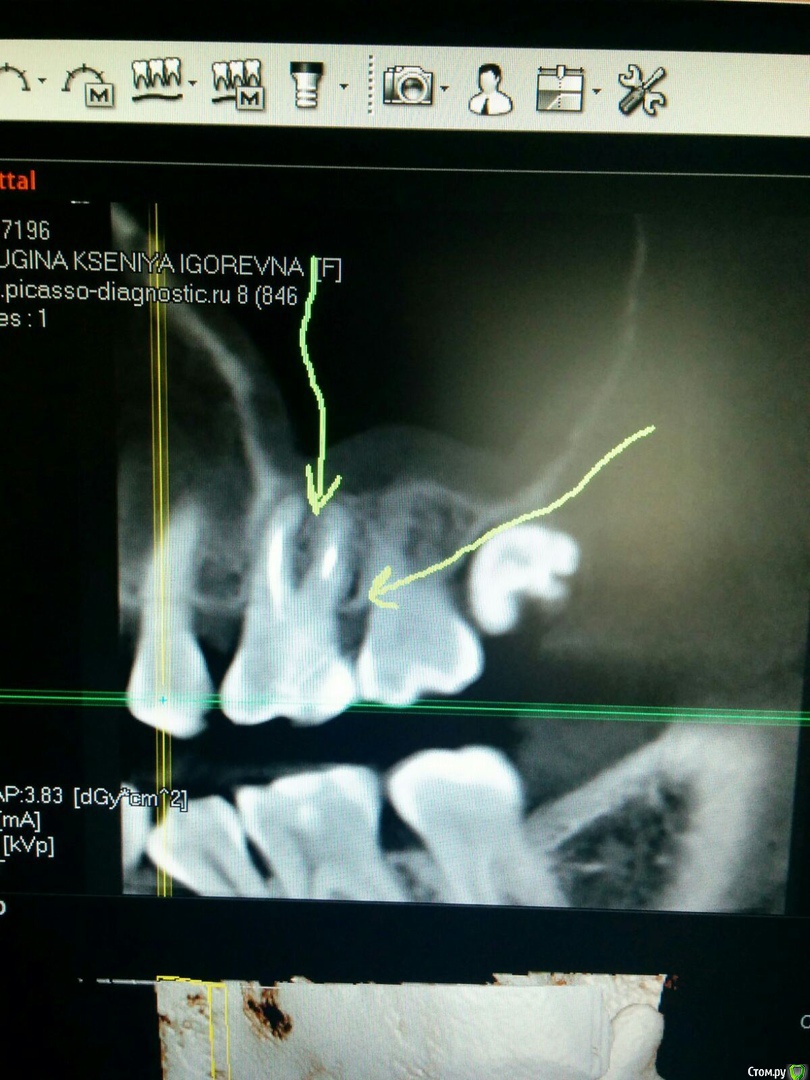

Добрый день, уважаемые доктора! И снова моя старая боль, история многострадального зуба, который пытаюсь спасти. Хоть кто-нибудь скажите мне, пожалуйста, что делать, у меня уже просто отчаяние. Расскажу подробнее, хотя ранее и писала тут по этому поводу. 10-12 лет назад мне депульпировали зуб. Врач перелечивал его изначально раза 3 не меньше, так как постоянно были боли. Потом зуб не болел лет 10-12. На протяжении всего этого периода регулярно чувствовала "нытьё" между этим зубом и соседним, десна воспалялась. На снимке всё норм было. В один момент этот зуб так разболелся, что хотелось залезть на стену. Реагировал на горячее, была болезненной перкуссия и вся десна отёкшей. Потом обострение прошло, НО осталась реакция на холодное и боли при попадании пищи в десневой карман у этого зуба. И спустя пару месяцев я решила этот зуб перелечить. Прилагаю снимки ДО перелечивания. Ходила с лекарством 3 недели, зуб не болел вообще (кстати, прошла реакция на холодное), был лишь дискомфорт между зубами, как обычно. Но хочу заметить, что соседние зубы без кариеса вообще, на них грешить не приходиться. Я тщательно слежу за гигиеной. Так вот, как только на постоянку запломбировали каналы, появилась ноющая боль, слабая такая и снова в области десны между зубами. Сделали снимок, на руках, увы, нет. Но я немного разбираюсь (ассистировала в своё время). Каналы запломбированы идеально, небольшое затемнение у нёбного корня. Ну, оно и понятно за 3 недели не восстановится. Сейчас снова беспокоит эта проклятая десна с карманом у этого зуба. Попадает еда - больно. И нажимаю языком с нёбной стороны десны - дискомфорт и слабая боль (уже не связанная с приёмом пищи). Что делать? Ума не приложу. Врач говорит, что там всё сделано грамотно и болеть не должно. Якобы это от гайморовой пазухи может быть. Но тогда, почему этот карман такое даёт? Я подозревала маргинальный периодонтит, но врач опровергла. Говорит, что инструмент глубоко сильно не заходит. Короче говоря, я в полном нокауте и не знаю, что делать. перелечивать врач не видит смысла, зубного камня нет. Боль усиливается немного сегодня, но у меня гайморит немного обострился ещё, может и это. Пока врач поставила пломбу так, чтобы ничего не забивалось, даже нить зубная не проходит между зубами. Но щель снизу есть - так что еда иногда всё же попадает. Как быть в этой сложной ситуации? Подскажите, пожалуйста.Удалять этот зуб не хочу. Все к кому обращалась, разводят руками. Говорят, что странный случай.